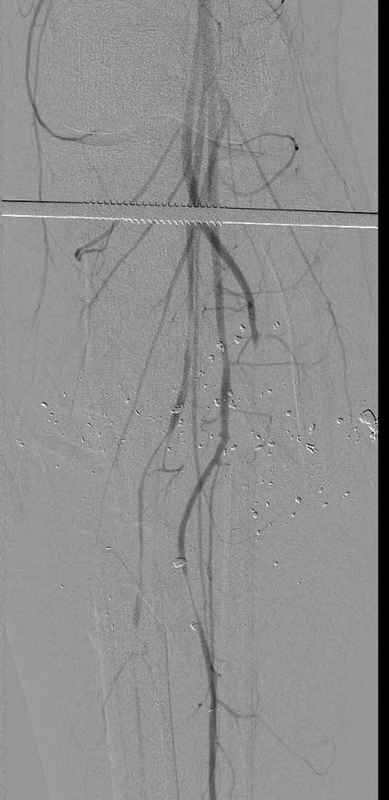

Уважаемые коллеги, Современная тактика лечения огнестрельных переломов вызывает споры. Опыты многих стран доказывает, что открытые переломы можно успешно лечить с применением внутренних металлических конструкций, включая гвозди. В западных странах более 25 лет эту методику применяют для лечения огнестрельных переломов. После применения адекватных методов по предупреждению осложнений, например, после промывания ран, огнестрельные переломы можно стабилизировать без боязни инфицирования. Здесь представлен больной 27 лет с ранениями, включая огнестрельный перелом большеберцовой кости. Стандартный аьгоритм: 11.08.09 доставлен в операционную, Irrigation&Debridment c фиксацией Наружным Фиксатором и вакуумирование VAC; службой травмы пройзведена ангиография с негативным результатом. (снимки 1-10) 14.08.09 повторная Irrigation&Debridment (чувстительственность из раны негативная) со сменой фиксации на медуллярный гвоздь и вакуумирование VAC 18.08 и 21.08.09 Irrigation&Debridment с сменой е VAC, после высеялся MRSA in thio т.е. на специальных срезах небольшое количество (11-13) 25.08.09 повторная Irrigation&Debridment. Пластик хирург не стал рисковать с Soleus flap из-за отечности, и применен Gastric flap, кожная пластика на медиальную и латеральную рану; аллографт из костных стружек с BMP. Поверхность вакуумирована VAC системой на 4 дня (14-16) Финальные снимки сделаем на днях. Djoldas Kuldjanov, MDDepartment of Orthopedic SurgerySt. Louis University Medical Center